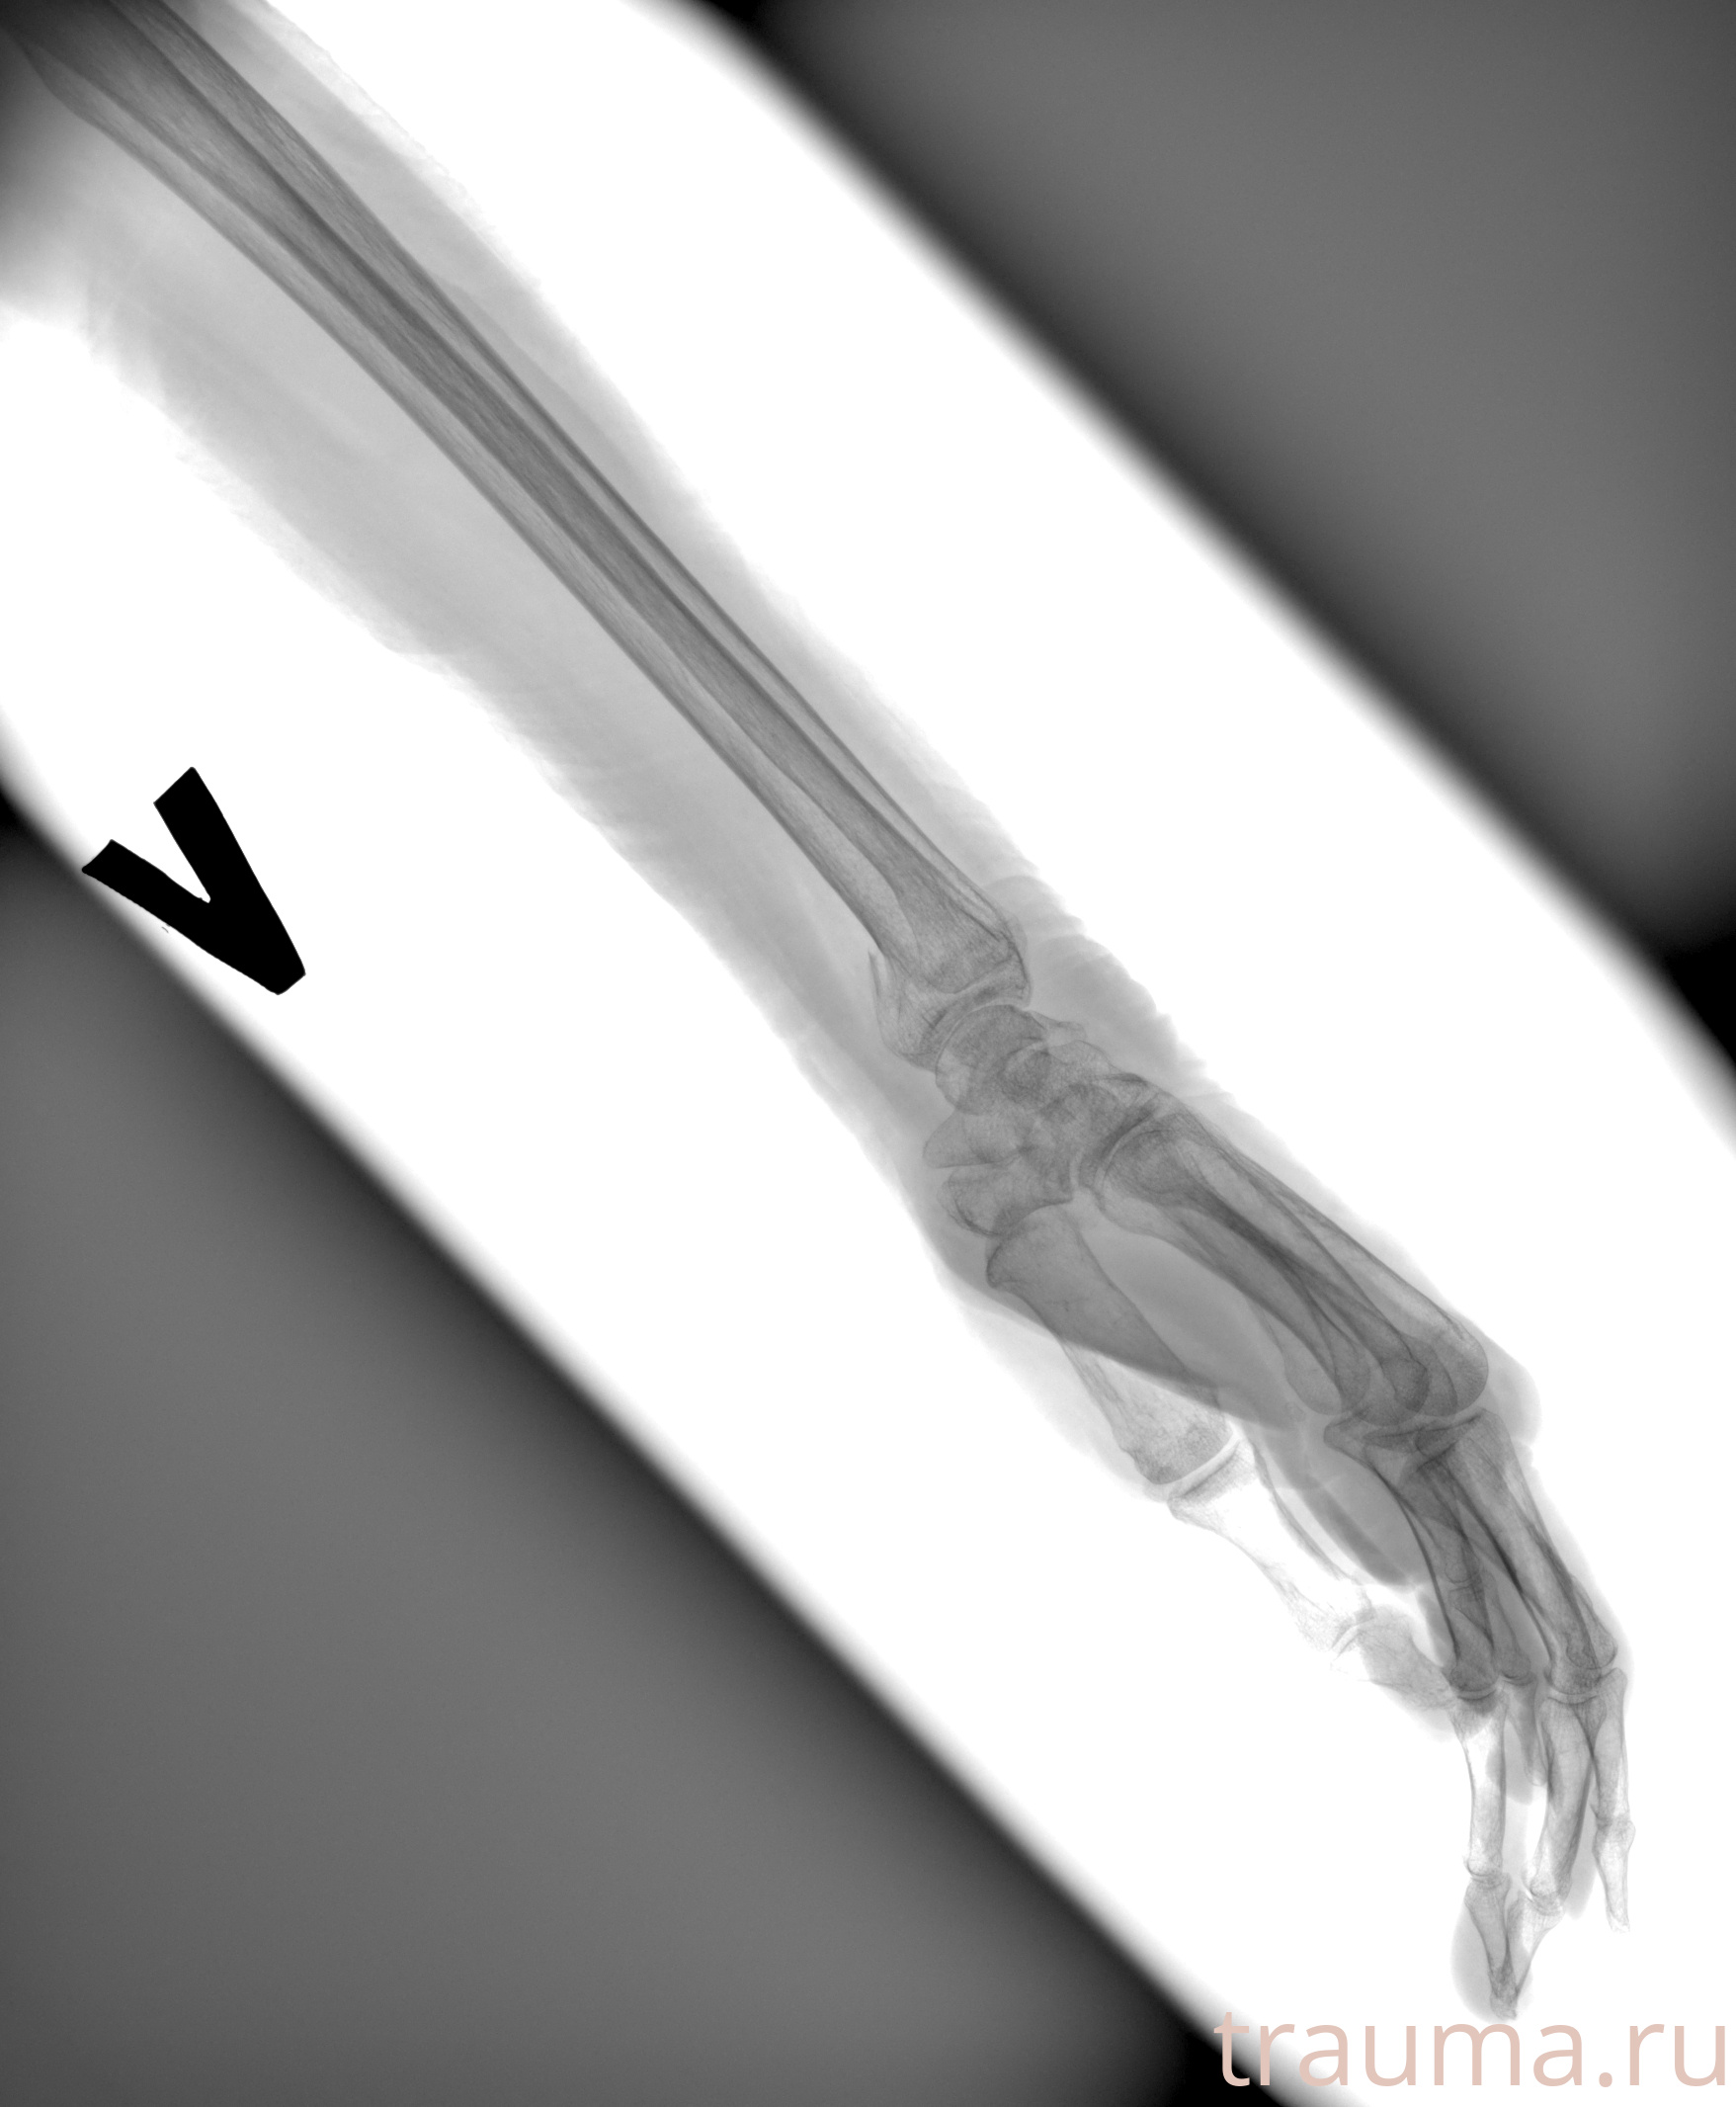

Рентгенограммы

Рентген на дому: по вашему адресу приезжает врач-рентгенолог, травматолог-ортопед с мобильным рентгеновским аппаратом, проводит диагностику травмы или заболевания, делает необходимые рентгенограммы, дает рекомендации по дальнейшему лечению. Получить качественные снимки в домашних условиях возможно благодаря уникальной методике, разработанной МосРентген Центром для института  Склифосовского